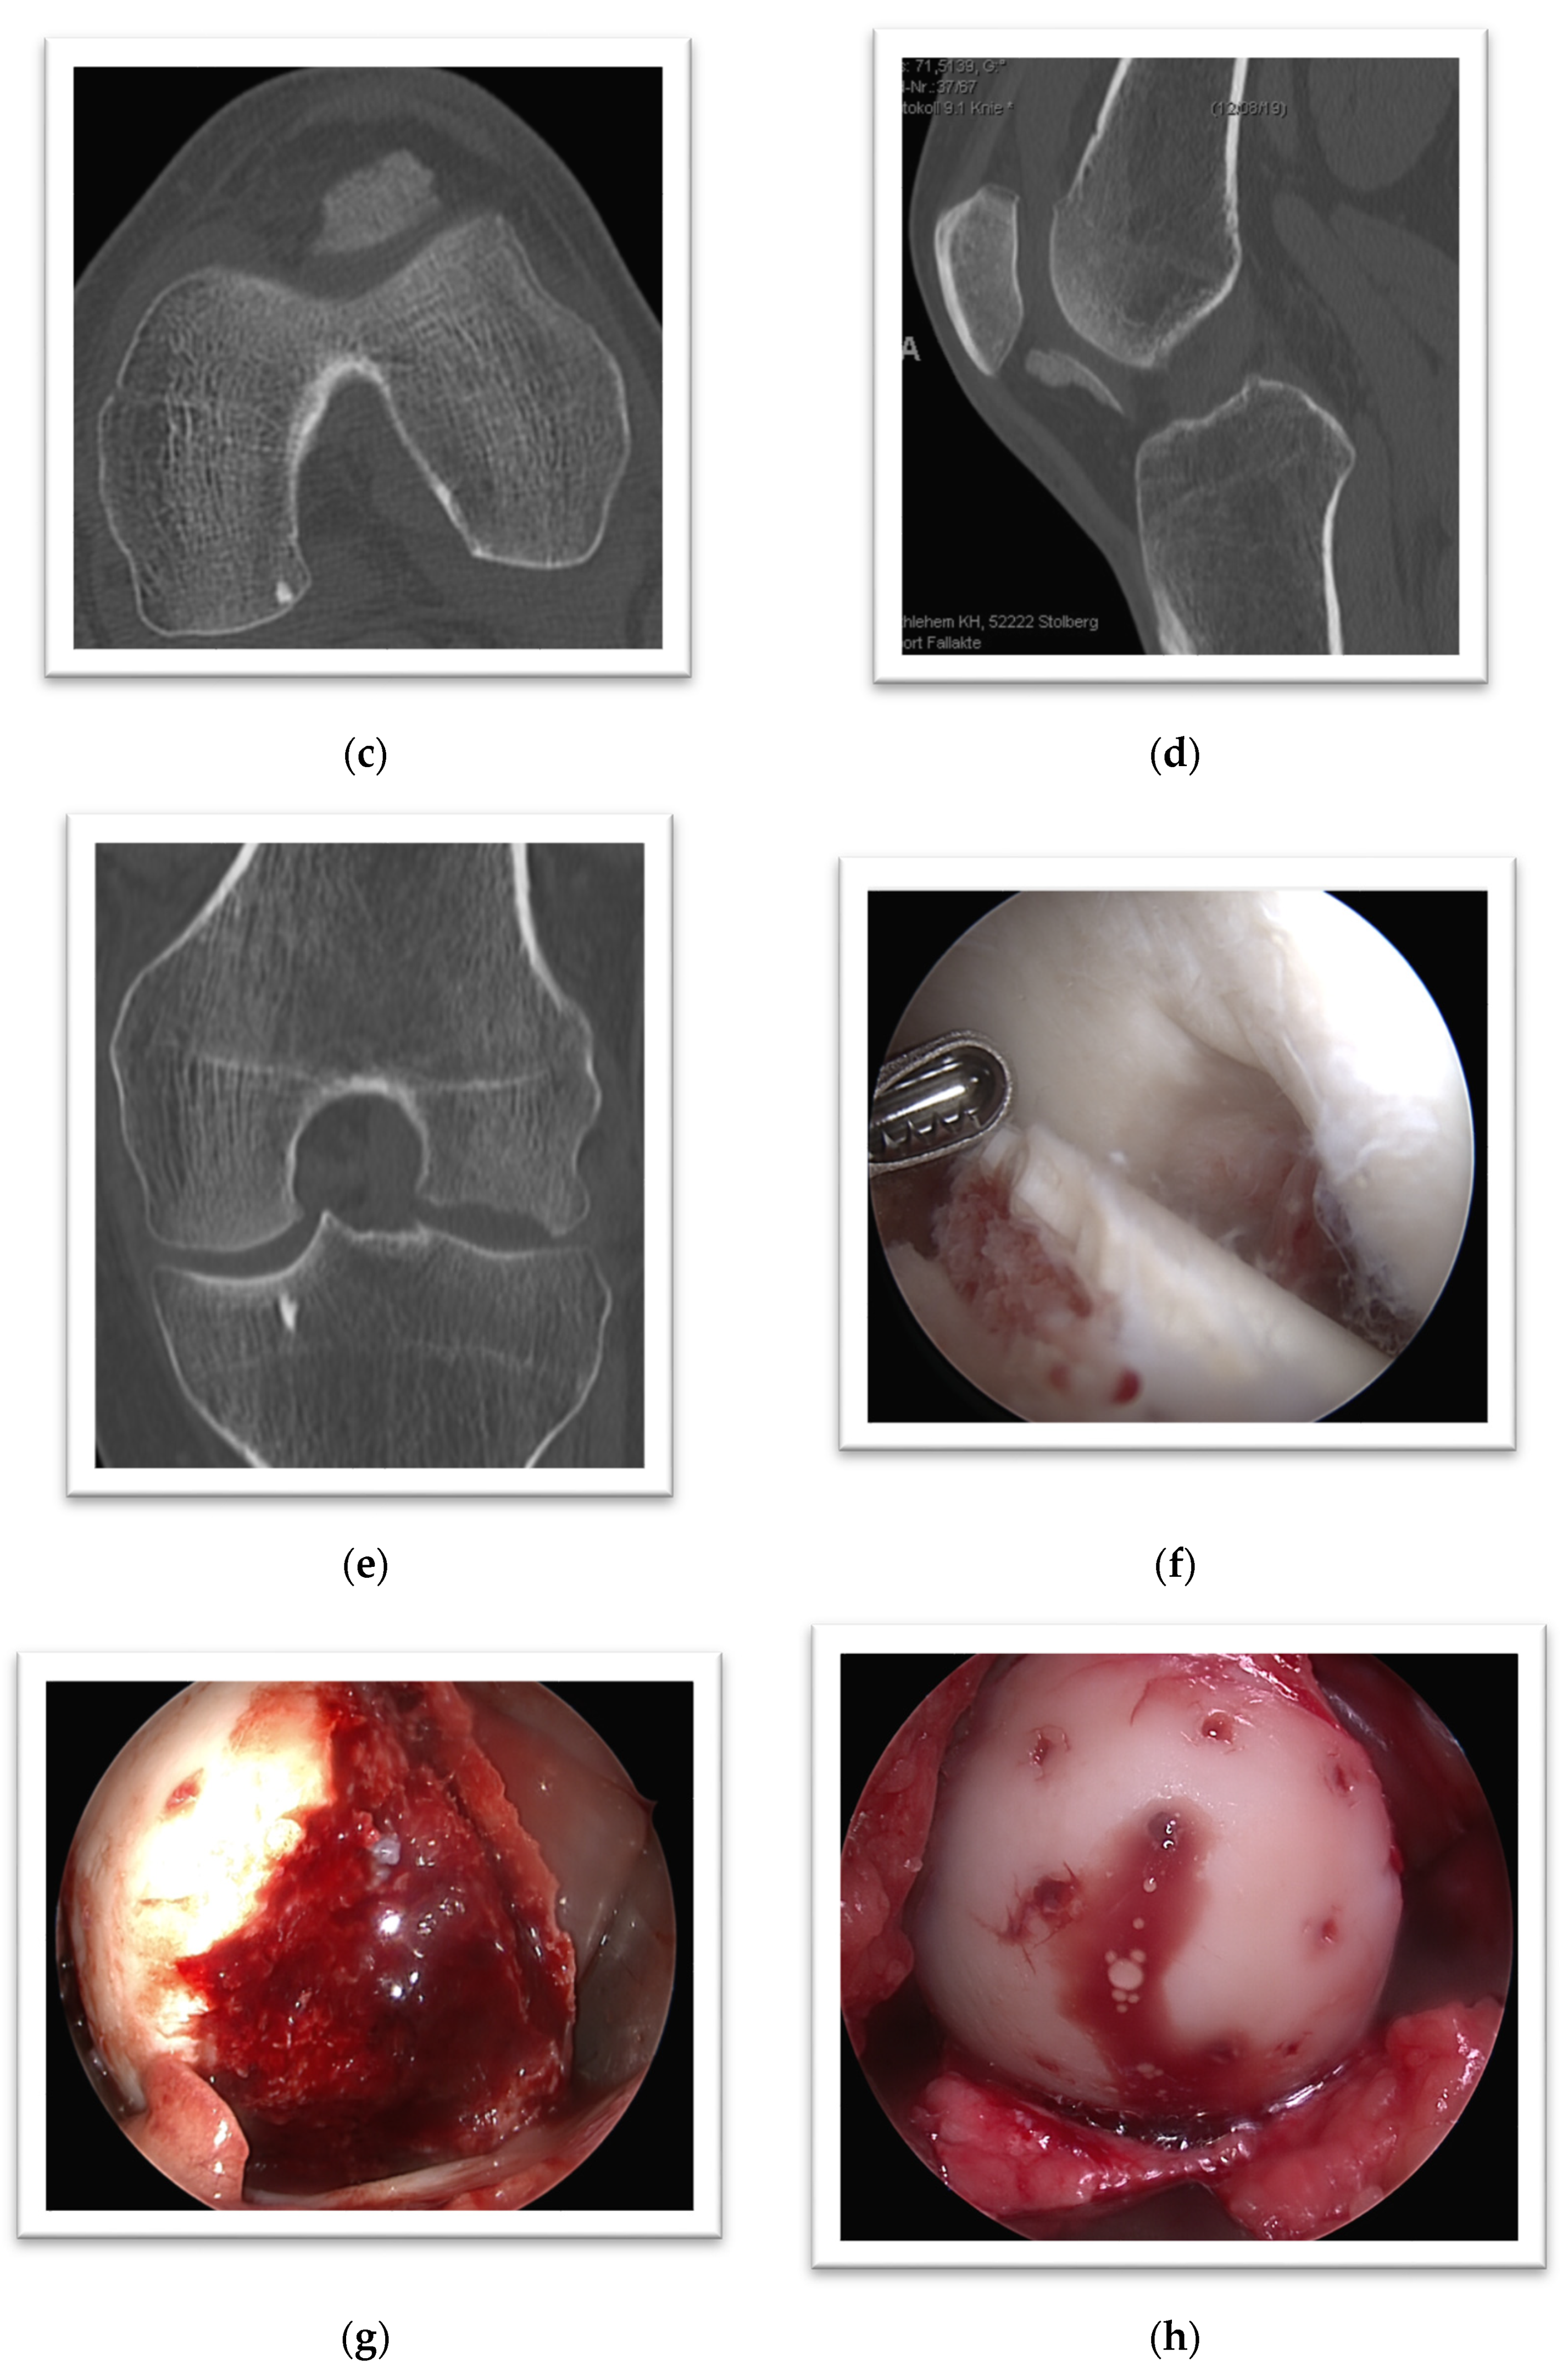

3. Case Presentation

4. Case Presentation

5. Case Presentation